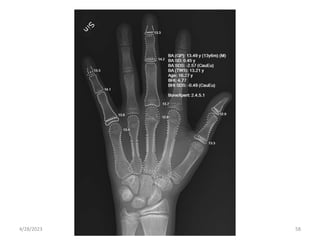

C. Bone Age

• evaluate growth and maturity and to diagnose and

manage pediatric disorders.

• For 1-8 yrs, bone age is determined by examining

carpal bones in X-ray of left wrist.

• No. of osification centres in wrist = Age(yrs)+1

Age X-ray

New born Knee, Ankle

3-9 months Shoulder

3 yrs Wrist

12-16 yrs Elbow, Hip

4/28/2023 56

• #57 pediatric endocrinology but also in orthodontics and pediatric orthopedics. because the hand and wrist possess many bones and taking radiographs of the hand and wrist is easy. One reason is that most people are right-handed, and therefore, the right hand is more likely to be injured than the left hand (1). Another reason is that it was determined that physical measurements should be performed on the left side rather than the right side of the body at the conferences of physical anthropologists in the early 1900s

• #58 The hand and wrist bones consist of the radius, ulna, 19 short bones (5 metacarpals and 14 phalanges) and 7 carpals. Bones are formed by endochondral ossification in the radius, ulna and short bones and by intramembranous ossification in the carpal bones. The maturation rates of the carpals vary among individuals. The completion of maturation occurs earlier in the carpals compared with the long and short bones, and intramembranous ossification is less dependent on GH than endochondral ossification. Therefore, the carpals are not suitable for bone age assessment.